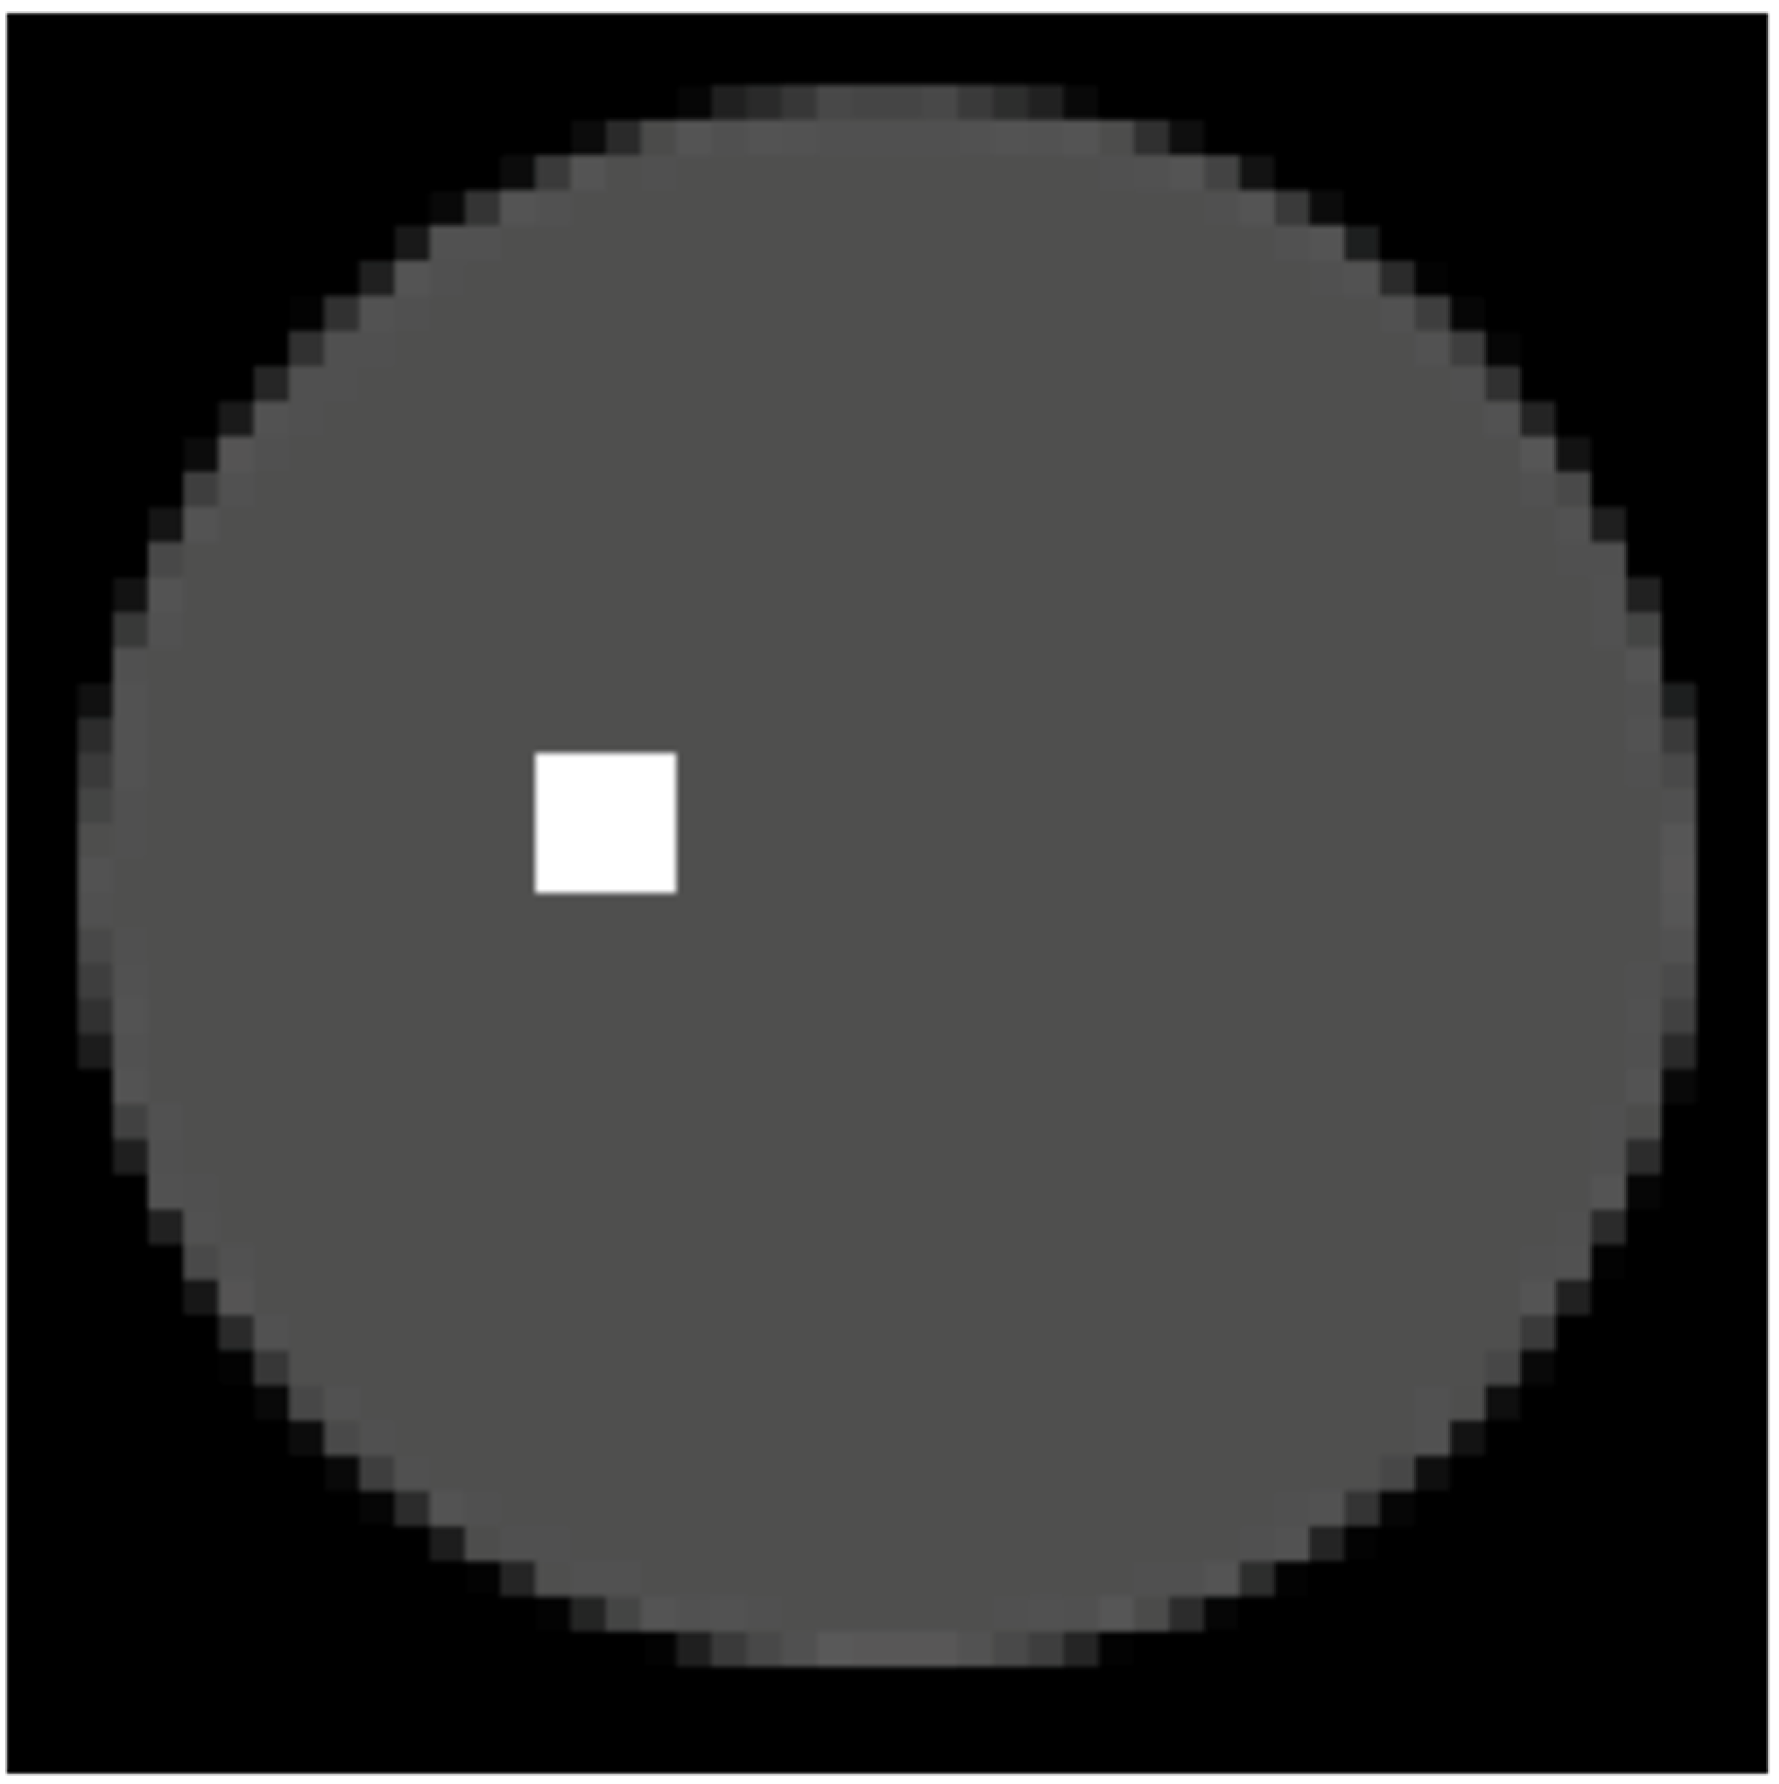

We assumed an imaging area with a lattice system of n = 50, that is, a 50 × 50-pixel grid with a spherical head phantom with a diameter of 46 pixels placed within this area. Assuming that the diameter of the head phantom was 20 cm, the actual size of each pixel was 0.432 cm2. Furthermore, a cancerous lesion (i.e., radiation source) was placed within the phantom. The lesion size was set to 4 × 4 pixels (=1.742 cm2). Figure 1 shows a case where the cancerous lesion was positioned slightly to the upper left of the center.

In Figure 1, the black areas represent regions outside the head, the grey areas indicate normal cells, and the white areas denote tumor cells. If the brightness levels of the black and white regions are set to 0 and 1, respectively, the brightness level of the grey areas is 0.31.

The ratio of boron accumulation in tumor cells to that in normal cells (T/N ratio) was equal to the ratio of the pixel values (source intensity) of tumor cells to that of normal cells; in this system, it was calculated as 1/0.31 (=3.2) [24].

Figure 1. Spherical head phantom and cancerous lesion within the imaging area (50 × 50 pixels).